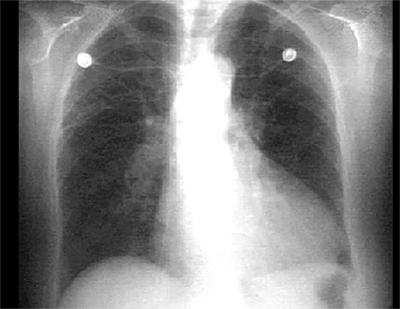

X Rays

PA and Lateral

Click on the xray to enlarge it.

Choose the best interpretation of the chest X ray:

Calcified coronary arteries

Normal

Pleural effusion

Pulmonary venous congestion

Left ventricular enlargement and dilated aorta